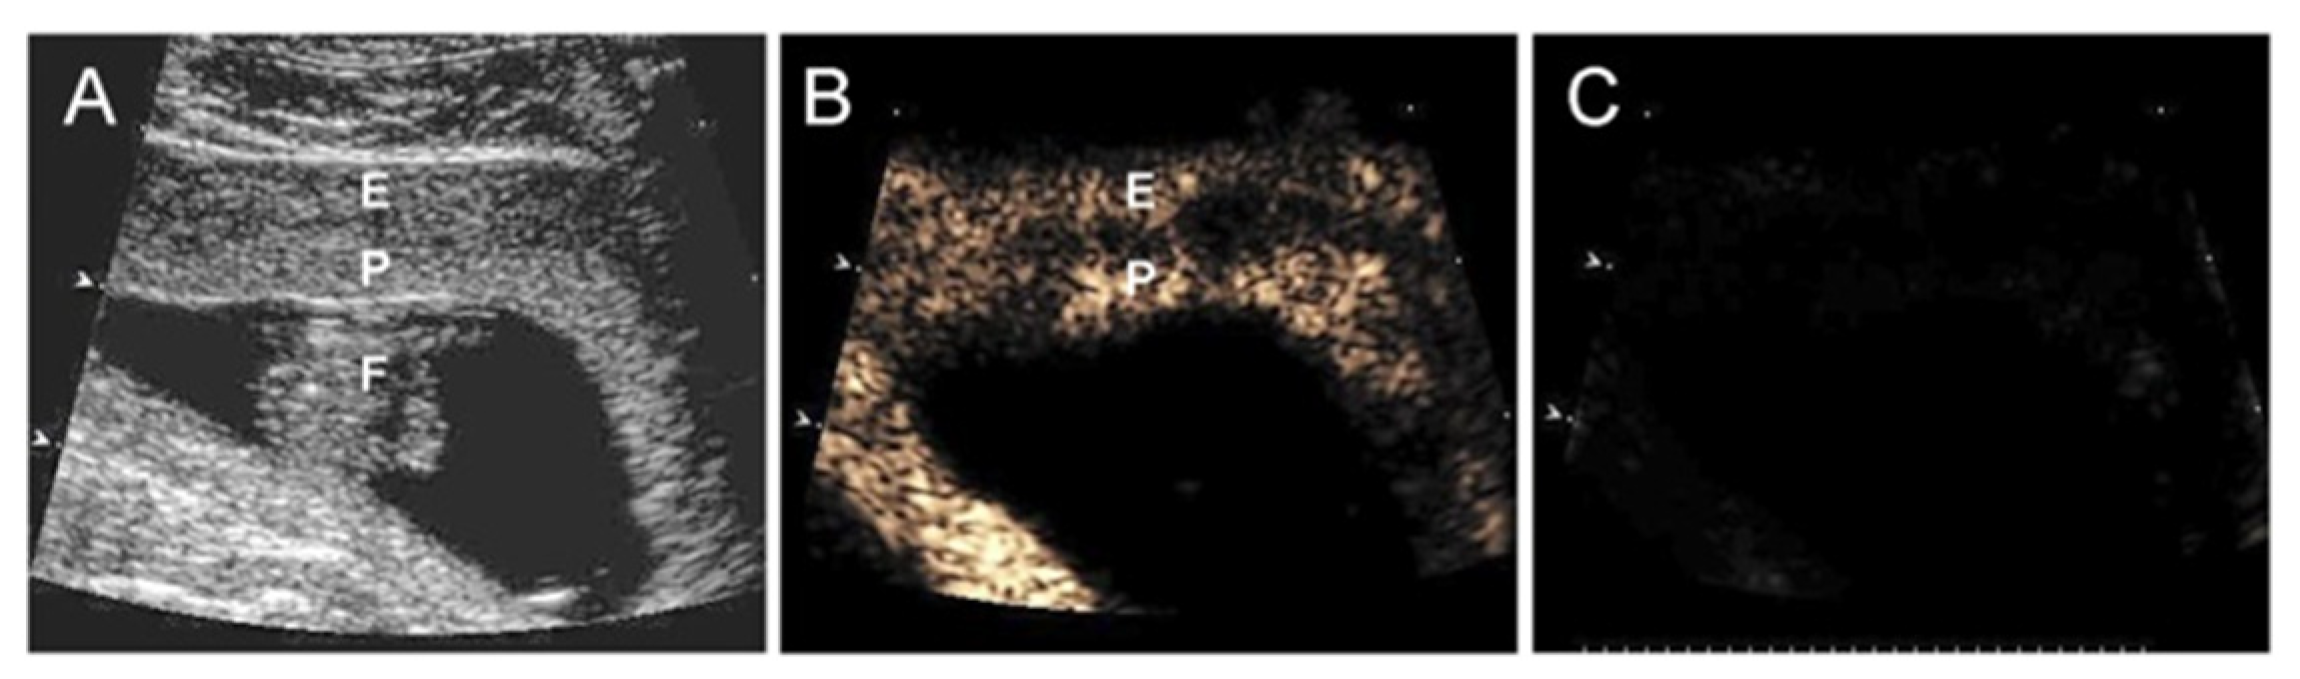

- Turan, O.; Babischkin, J.S.; Aberdeen, G.W.; Turan, S.; Harman, C.; Pepe, G.J.; Albrecht, E.D. B-flow/Spatio temporal image correlation M-mode: A novel ultrasound method that detects a decrease in spiral artery luminal diameter in the first trimester in a primate model of impaired spiral artery remodeling. Ultrasound Obstet. Gynecol. 2021. ahead of print. [Google Scholar] [CrossRef]

- Babischkin, J.S.; Aberdeen, G.W.; Lindner, J.R.; Bonagura, T.W.; Pepe, G.J.; Albrecht, E.D. Vascular endothelial growth factor delivery to placental basal plate promotes uterine artery remodeling in the primate. Endocrinology 2019, 160, 1492–1505. [Google Scholar] [CrossRef]

- Roberts, V.H.; Lo, J.O.; Salati, J.A.; Lewandowski, K.S.; Lindner, J.R.; Morgan, T.K.; Frias, A.E. Quantitative assessment of placental perfusion by contrast-enhanced ultrasound in macaques and human subjects. Am. J. Obstet. Gynecol. 2016, 214, 369.e1–369.e8. [Google Scholar] [CrossRef]

- Roberts, V.H.; Frias, A.E. Contrast-enhanced ultrasound for the assessment of placental development and function. Biotechniques 2020, 69, 392–399. [Google Scholar] [CrossRef]